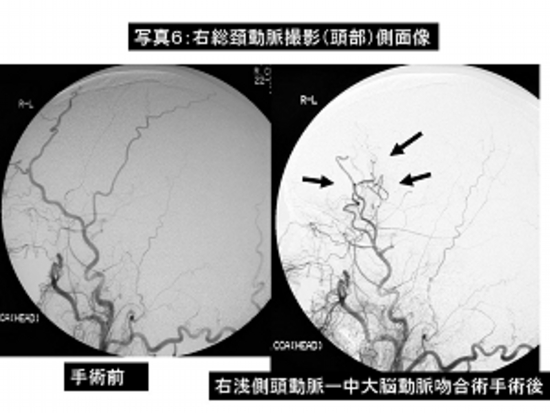

写真6:右内頸動脈閉塞症に対する右浅側頭動脈—中大脳動脈吻合術。

左は手術前の脳血管撮影、右は手術後の脳血管撮影で頭蓋外動脈(浅側頭動脈)から頭蓋内血管(中大脳動脈)への良好な血流が確認されます(→)。

患者さんは特に症状はなく自力歩行で退院されました。